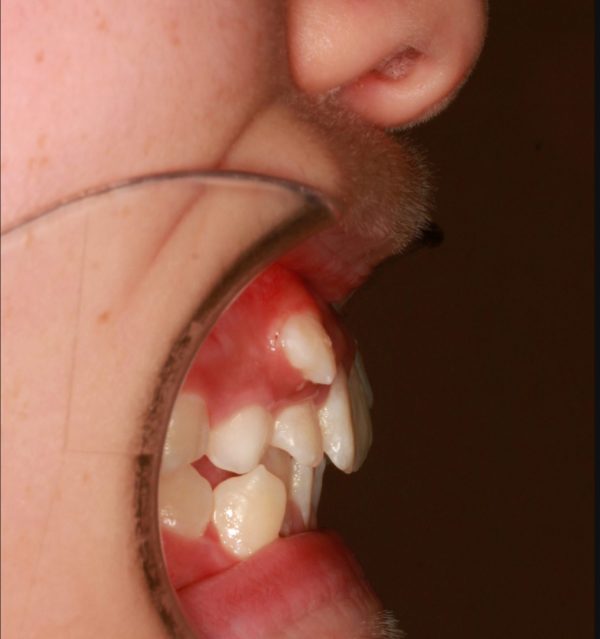

13歳 女性「八重歯 を治したい」( 叢生 ・ 上下顎前突症 )

13歳の 女性です。

「”八重歯” を治してほしい」との事で来院されました。

典型的な ”八重歯”です。

犬歯が 歯列外に押し出されています。

レントゲン写真をみても 歯が入り乱れて生えています

”八重歯”がとにかく 気になりますが・・・

正面から見ると、口もとが出ています。”八重歯” の影響です。

口もとの”もっさり感”が目立ちますね。

横からみると 上下の口唇が 出ています。

とくに、下唇のめくれあがりが目立ちます。

叢生を伴う 上下顎前突症です

”八重歯”と 口もとの 出っ張り感を治したいとの事で

上下左右の 小臼歯抜歯を行い 前歯を後方に移動させました。

2019年の7月5日にスタートして 、2021年の2月15日に 終 了 しました。

治療期間は 20か月でした。

”八重歯”は すっかりと解消され、上顎の前後的な距離が短くなりました。

この効果で前歯は 下がり、口もとの状態は改善しました。

口唇がずいぶんと下がり、エステティックラインの内側に収まりました

口もと の出っ張り感も 解消され、お口が閉じやすくなったとの事です。

全体的に”スッキリ”とした口もとになりました。

下がっていた 口角が上がりました。

笑顔の印象も大きく 大きく変わりました